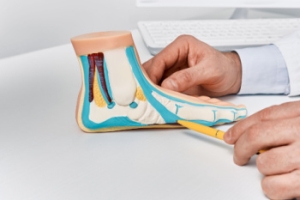

Heel pain is often associated with plantar fasciitis. The plantar fascia is a band of tissues that extends along the bottom of the foot. A rip or tear in this ligament can cause inflammation of the tissue.

Heel spurs are another cause of pain. When the tissues of the plantar fascia undergo a great deal of stress, it can lead to ligament separation from the heel bone, causing heel spurs.

Plantar Fasciitis

One of the main causes of heel pain is a condition known as plantar fasciitis. The plantar fascia is a band of tissue that extends along the bottom of the foot, from the toe to the bottom of the heel. A rip or tear in this ligament can cause inflammation of these tissues, resulting in heel pain. People who do not wear proper fitting shoes are often at risk of developing problems such as plantar fasciitis. Unnecessary stress from ill-fitting shoes, weight change, excessive running, and wearing non-supportive shoes on hard surfaces are all causes of plantar fasciitis.

A third cause of heel pain is a heel spur. A heel spur occurs when the tissues of the plantar fascia undergo a great deal of stress, leading to a separation of the ligament from the heel bone entirely. This results in a pointed fragment of bone on the ball of the foot, known as a heel spur.

Plantar fasciitis is a painful injury. It is inflammation of the plantar fascia, the thick band of tissue running from the heel to the base of the toes. If left untreated, it can lead to a degenerative disease called plantar fasciosis. There are several effective treatments for this ailment. Doctors often prescribe rest, massages, stretching, night splints, physical therapy, anti-inflammatory medication, corticosteroids or surgery, usually in that order. The most effective treatment for plantar fasciitis is orthotics, which offers foot support. Surgery is occasionally used as a last resort, but it comes with the risk of nerve damage and infection and often does not stop the pain.